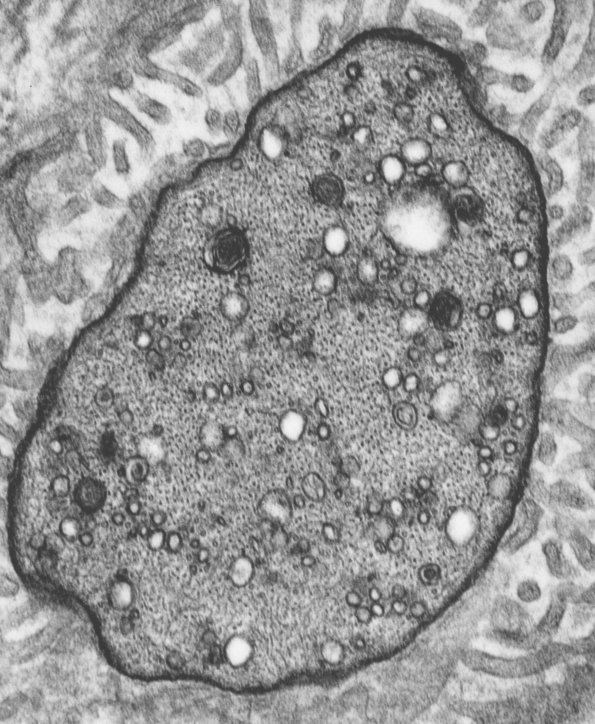

3A2 Closeup of Node of Ranvier - Copy

Higher magnification of image #3A1. (electron micrograph)